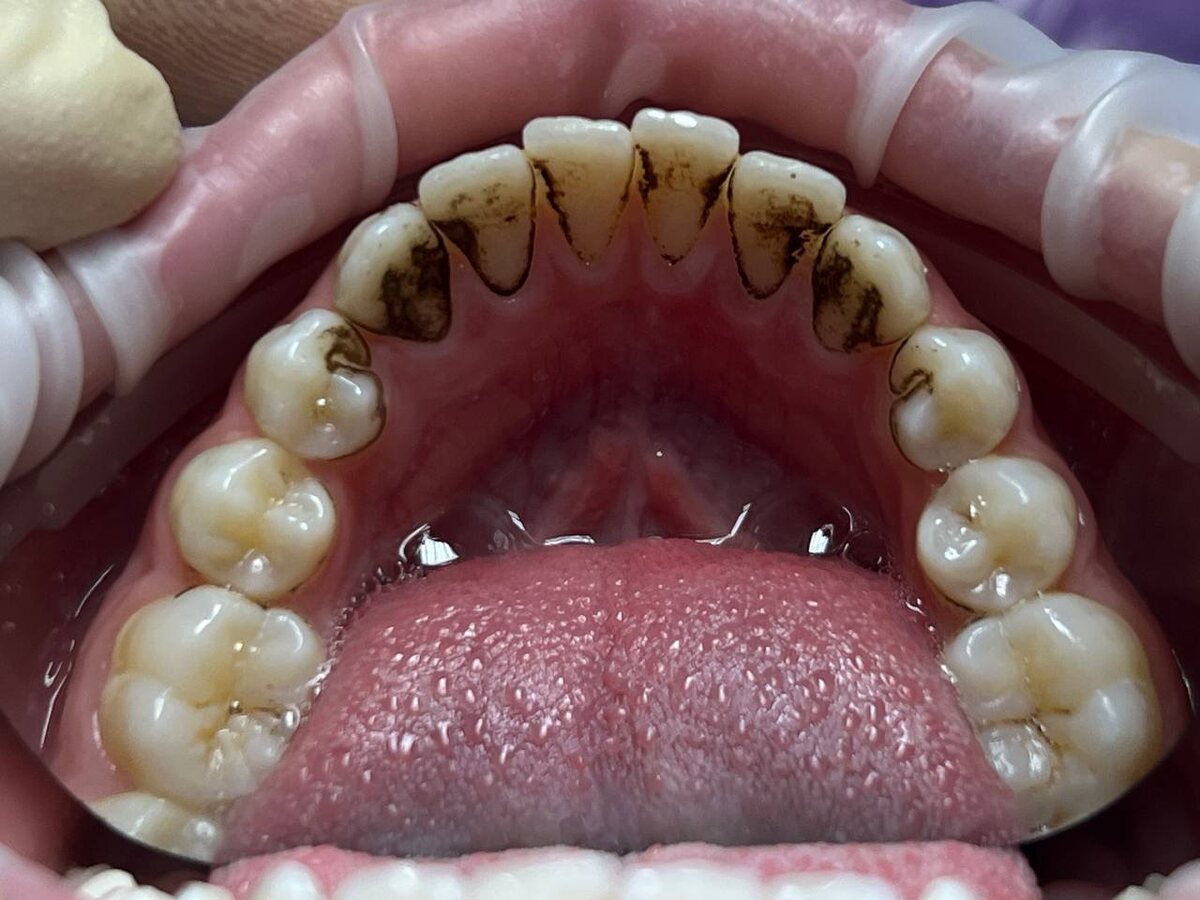

Налёт Присли — это особая форма зубного налёта, которая может возникнуть у детей и даже взрослых. Он обладает характерными признаками:

- Тёмный цвет — от насыщенного коричневого до почти чёрного.

- Образуется в основном вдоль линии дёсен и на внешней поверхности зубов.

- Не удаляется обычной зубной щёткой или зубной пастой.

- Хоть налёт и вызывает эстетический дискомфорт, зубы могут оставаться абсолютно здоровыми.